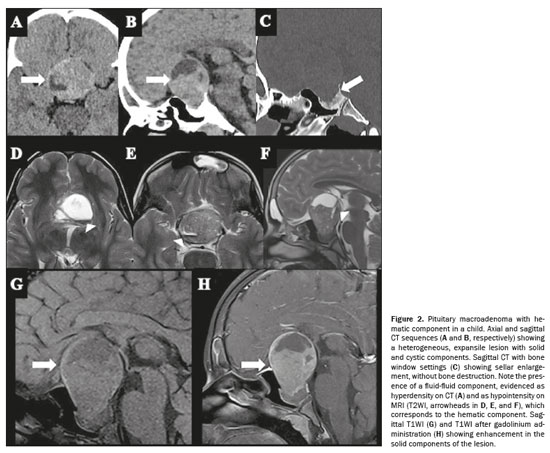

Less common imaging features of pituitary macroadenomasHemorrhages and areas of necrosisIntratumoral hemorrhage and ischemic infarction are common in larger PitNETs, which may result in hemorrhagic changes, cystic changes, or both, leading to various signal intensities on MRI

(25). Pituitary macroadenomas often have a complex internal structure with varying degrees of necrosis and cystic changes, which can alter the typical progression of hemoglobin degradation

(26). The presence of necrotic tissue can affect the breakdown and absorption of blood products, leading to atypical imaging findings

(27). Advanced MRI techniques capable of detecting an adenoma and its hemorrhagic changes, such as T2*WI gradient-echo sequences and phase-sensitive imaging, reveal that hemorrhages in pituitary macroadenomas can present with diverse appearances, such as “rim”, “mass”, “spot”, and “diffuse” patterns (Figure 2), which do not necessarily correlate with the standard phases of hemoglobin degradation

(26,28).

Hemorrhage occurs in up to 25% of pituitary tumors. In cases of hemorrhage, the hematic components appear as hyperintense on T1WI, hypointense on T2WI, hypointense on T2*WI, and hypointense on SWI

(6). It is clinically asymptomatic in most patients and can be focal or diffuse throughout the adenoma. There is also restricted diffusion due to the accumulation of intracellular hemorrhagic products

(6).

A fluid-fluid level within the adenoma is highly suggestive of hemorrhage, which may occur at a later stage due to the sedimentation of blood products. The finding also aids in the differential diagnosis of craniopharyngioma, which may exhibit a hyperintense signal on T1WI because of the presence of many proteins. However, a craniopharyngioma less commonly presents with hemorrhage and therefore does not typically exhibit a fluid-fluid level. Differentiating necrosis from cystic changes due to previous hemorrhage in the adenoma is not possible by CT, but rather by MRI, which has high sensitivity when a spin-echo pulse sequence with a short repetition time/echo time (TR/TE) is used. In such sequences, the cystic areas will be predominantly hypointense, with the signal intensity increasing in sequences with longer TR/TE values. Areas with subacute and chronic hematic content show high signal intensity on spin-echo sequences with short TR/TE values

(29). Although CT has no role in evaluating previous and subacute hemorrhage, it can aid in assessing acute bleeding

(29), especially within the first 24–48 h, when it can reveal hyperdensity (60–90 HU).